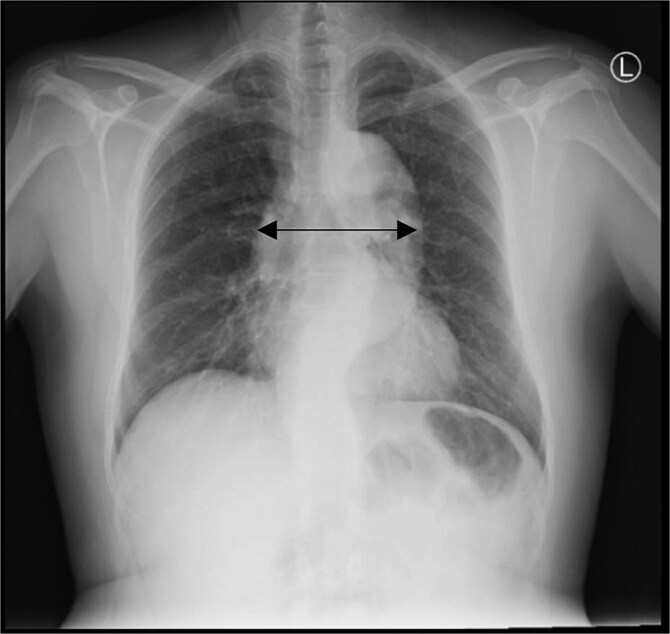

咯血是源自下呼吸道的血液的咳痰,有广泛的鉴别诊断,从良性疾病到危及生命的疾病,包括肺栓塞、严重感染和主动脉夹层。我们报告一位53岁男性,有高血压、慢性阻塞性肺病和吸烟史,以两天咯血史就诊于急诊科。尽管没有胸痛等典型症状,但胸部x线片显示纵隔增宽,并进行了增强CT血管造影。CT扫描证实是斯坦福B型主动脉夹层。在多学科审查后,医疗管理决定降压药和氨甲环酸。患者血流动力学保持稳定,并被转入进一步治疗。本病例提示,即使没有典型症状,主动脉夹层也应列入咯血的鉴别诊断。

Hemoptysis is the expectoration of blood originating from the lower respiratory tract and has a wide differential diagnosis, ranging from benign conditions to life-threatening diseases that include pulmonary embolism, severe infections, and aortic dissection. We present a 53-year-old male with a history of hypertension, COPD, and smoking, presenting to the emergency department with a two-day history of hemoptysis. In spite of the absence of classical symptoms such as chest pain, his chest X-ray showed mediastinal widening, and further imaging was performed with contrast-enhanced CT angiography. The CT scan confirmed a Stanford Type B aortic dissection. After multidisciplinary review, medical management was decided upon with antihypertensive medications and tranexamic acid. The patient remained hemodynamically stable and was transferred for further management. This case indicates the inclusion of aortic dissection in the differential diagnosis of hemoptysis, even without classic symptoms.